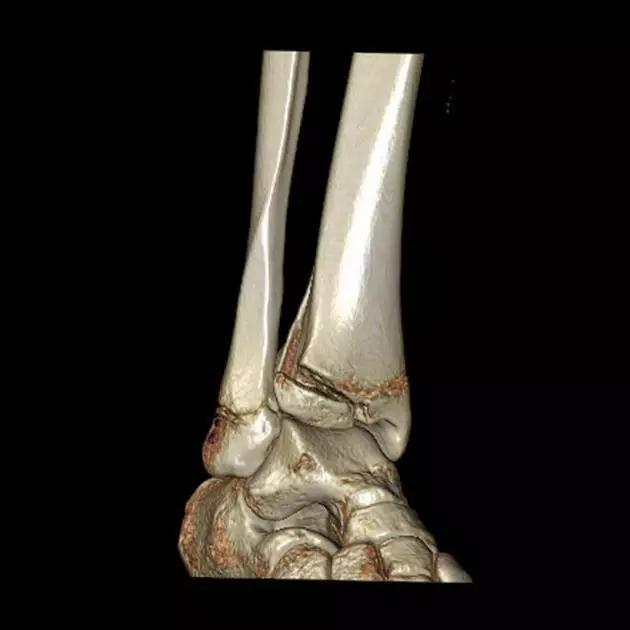

6. Pilon 骨折

涉及负重关节面(胫距关节面)与胫骨远侧干骺端的骨折。其典型特征是干骺端存在不同程度的压缩、干骺端的压缩粉碎性骨折不稳定、原发性关节软骨损伤以及永久性关节面不平整导致预后不良。

pilon 骨折正位片

pilon 骨折侧位片

pilon 骨折三维 CT 表现